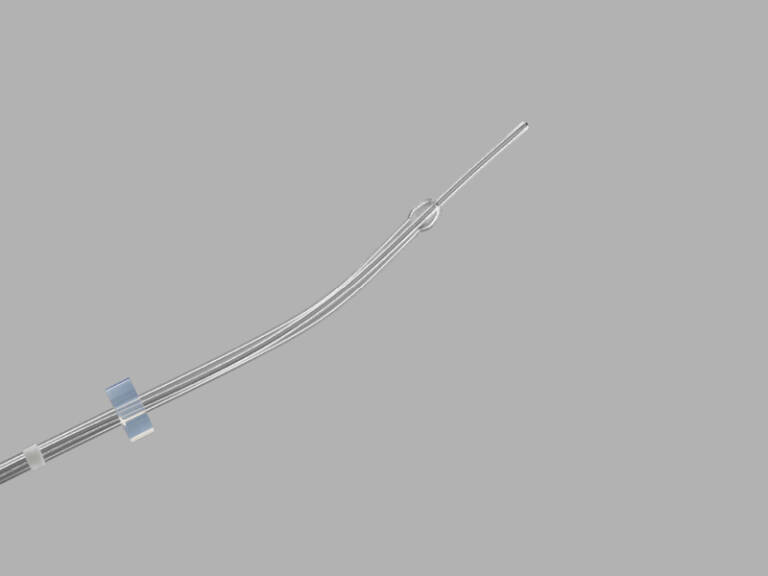

Guardia™ Access Embryo Transfer Catheter

DESCRIPTION:

Used to place in vitro fertilized (IVF) embryos into the uterine cavity.

- The guide catheter is curved to facilitate insertion.

- The guide catheter’s rounded bulb tip eases passage through the cervix.

- The transfer catheter is soft and flexible.The Microvol™ technology minimizes the volume of media that is required.

- The cervical stop comes set at 4 cm and can be adjusted to 5 cm. The catheters are packaged in separate sterile pouches.